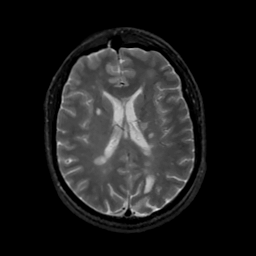

MR Study #13, May 19, 1991 -- Slice #30